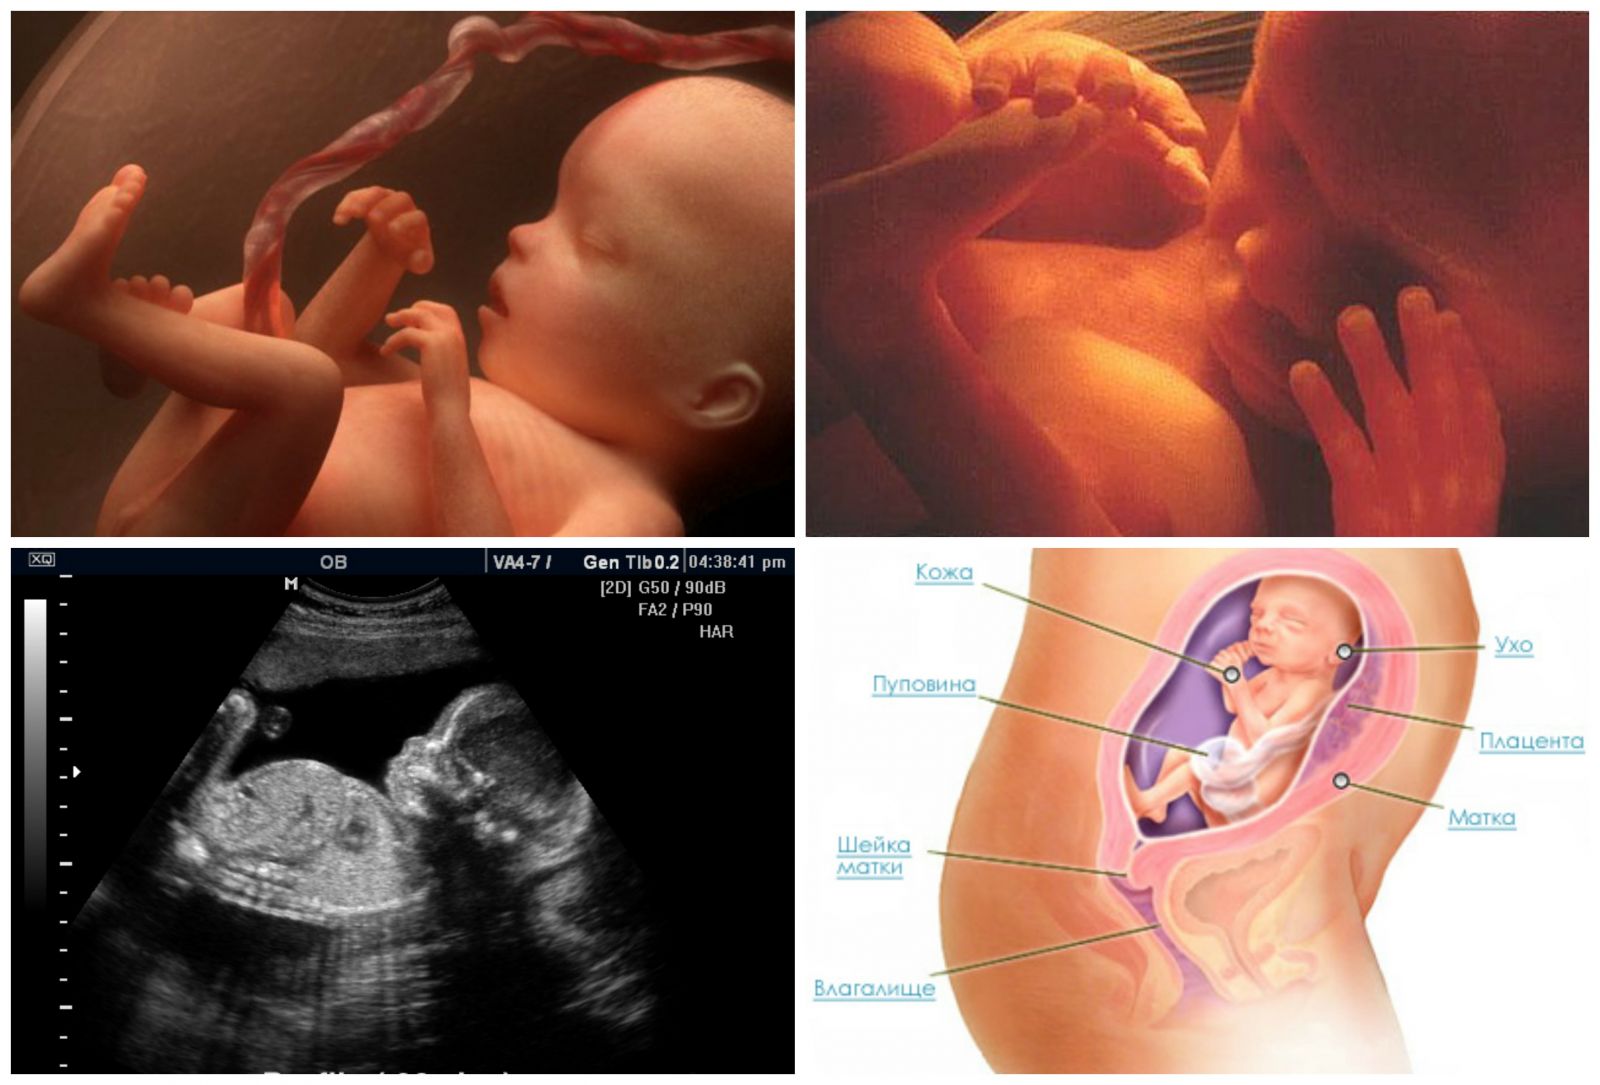

Важный этап: развитие малыша на 20-й неделе беременности

Раздел: Снимки-откровения